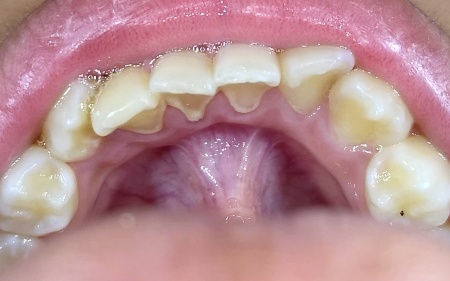

治療後

歯石は保険診療内のクリーニングで除去できることをお伝えし、治療に同意いただきました。

まず、超音波を利用した機械と専用の器具を用いて、歯石を丁寧に取り除きました。

歯石の除去後は、器具の刺激により歯の表面に微細な傷ができることがあります。

傷を放置すると、新たな歯石や汚れが再び付着しやすくなるため、回転するブラシを用いて歯を磨くポリッシングを行い、表面を滑らかに仕上げました。

最後に、歯石の再付着を予防するため、患者様と保護者様には歯石が付きやすい部分の説明や、歯ブラシの正しい当て方・動かし方の指導を実施し、治療を終了しています。